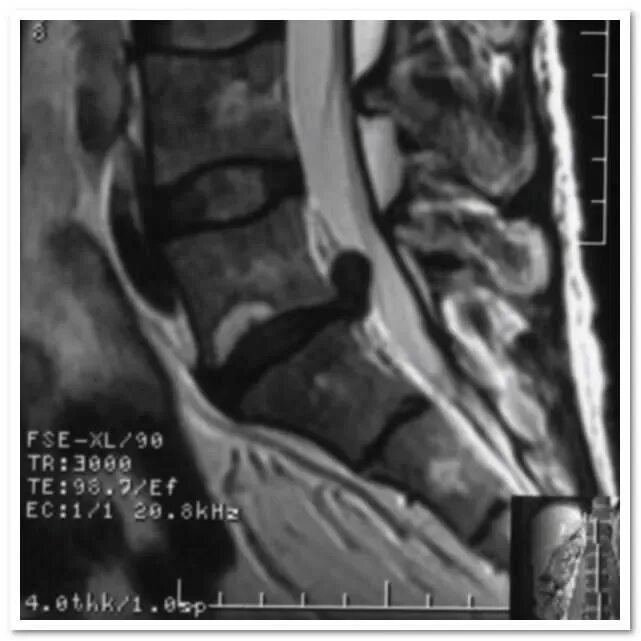

Грыжа диска мрт